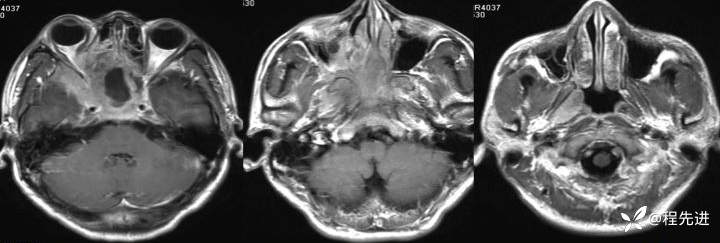

T1:

img